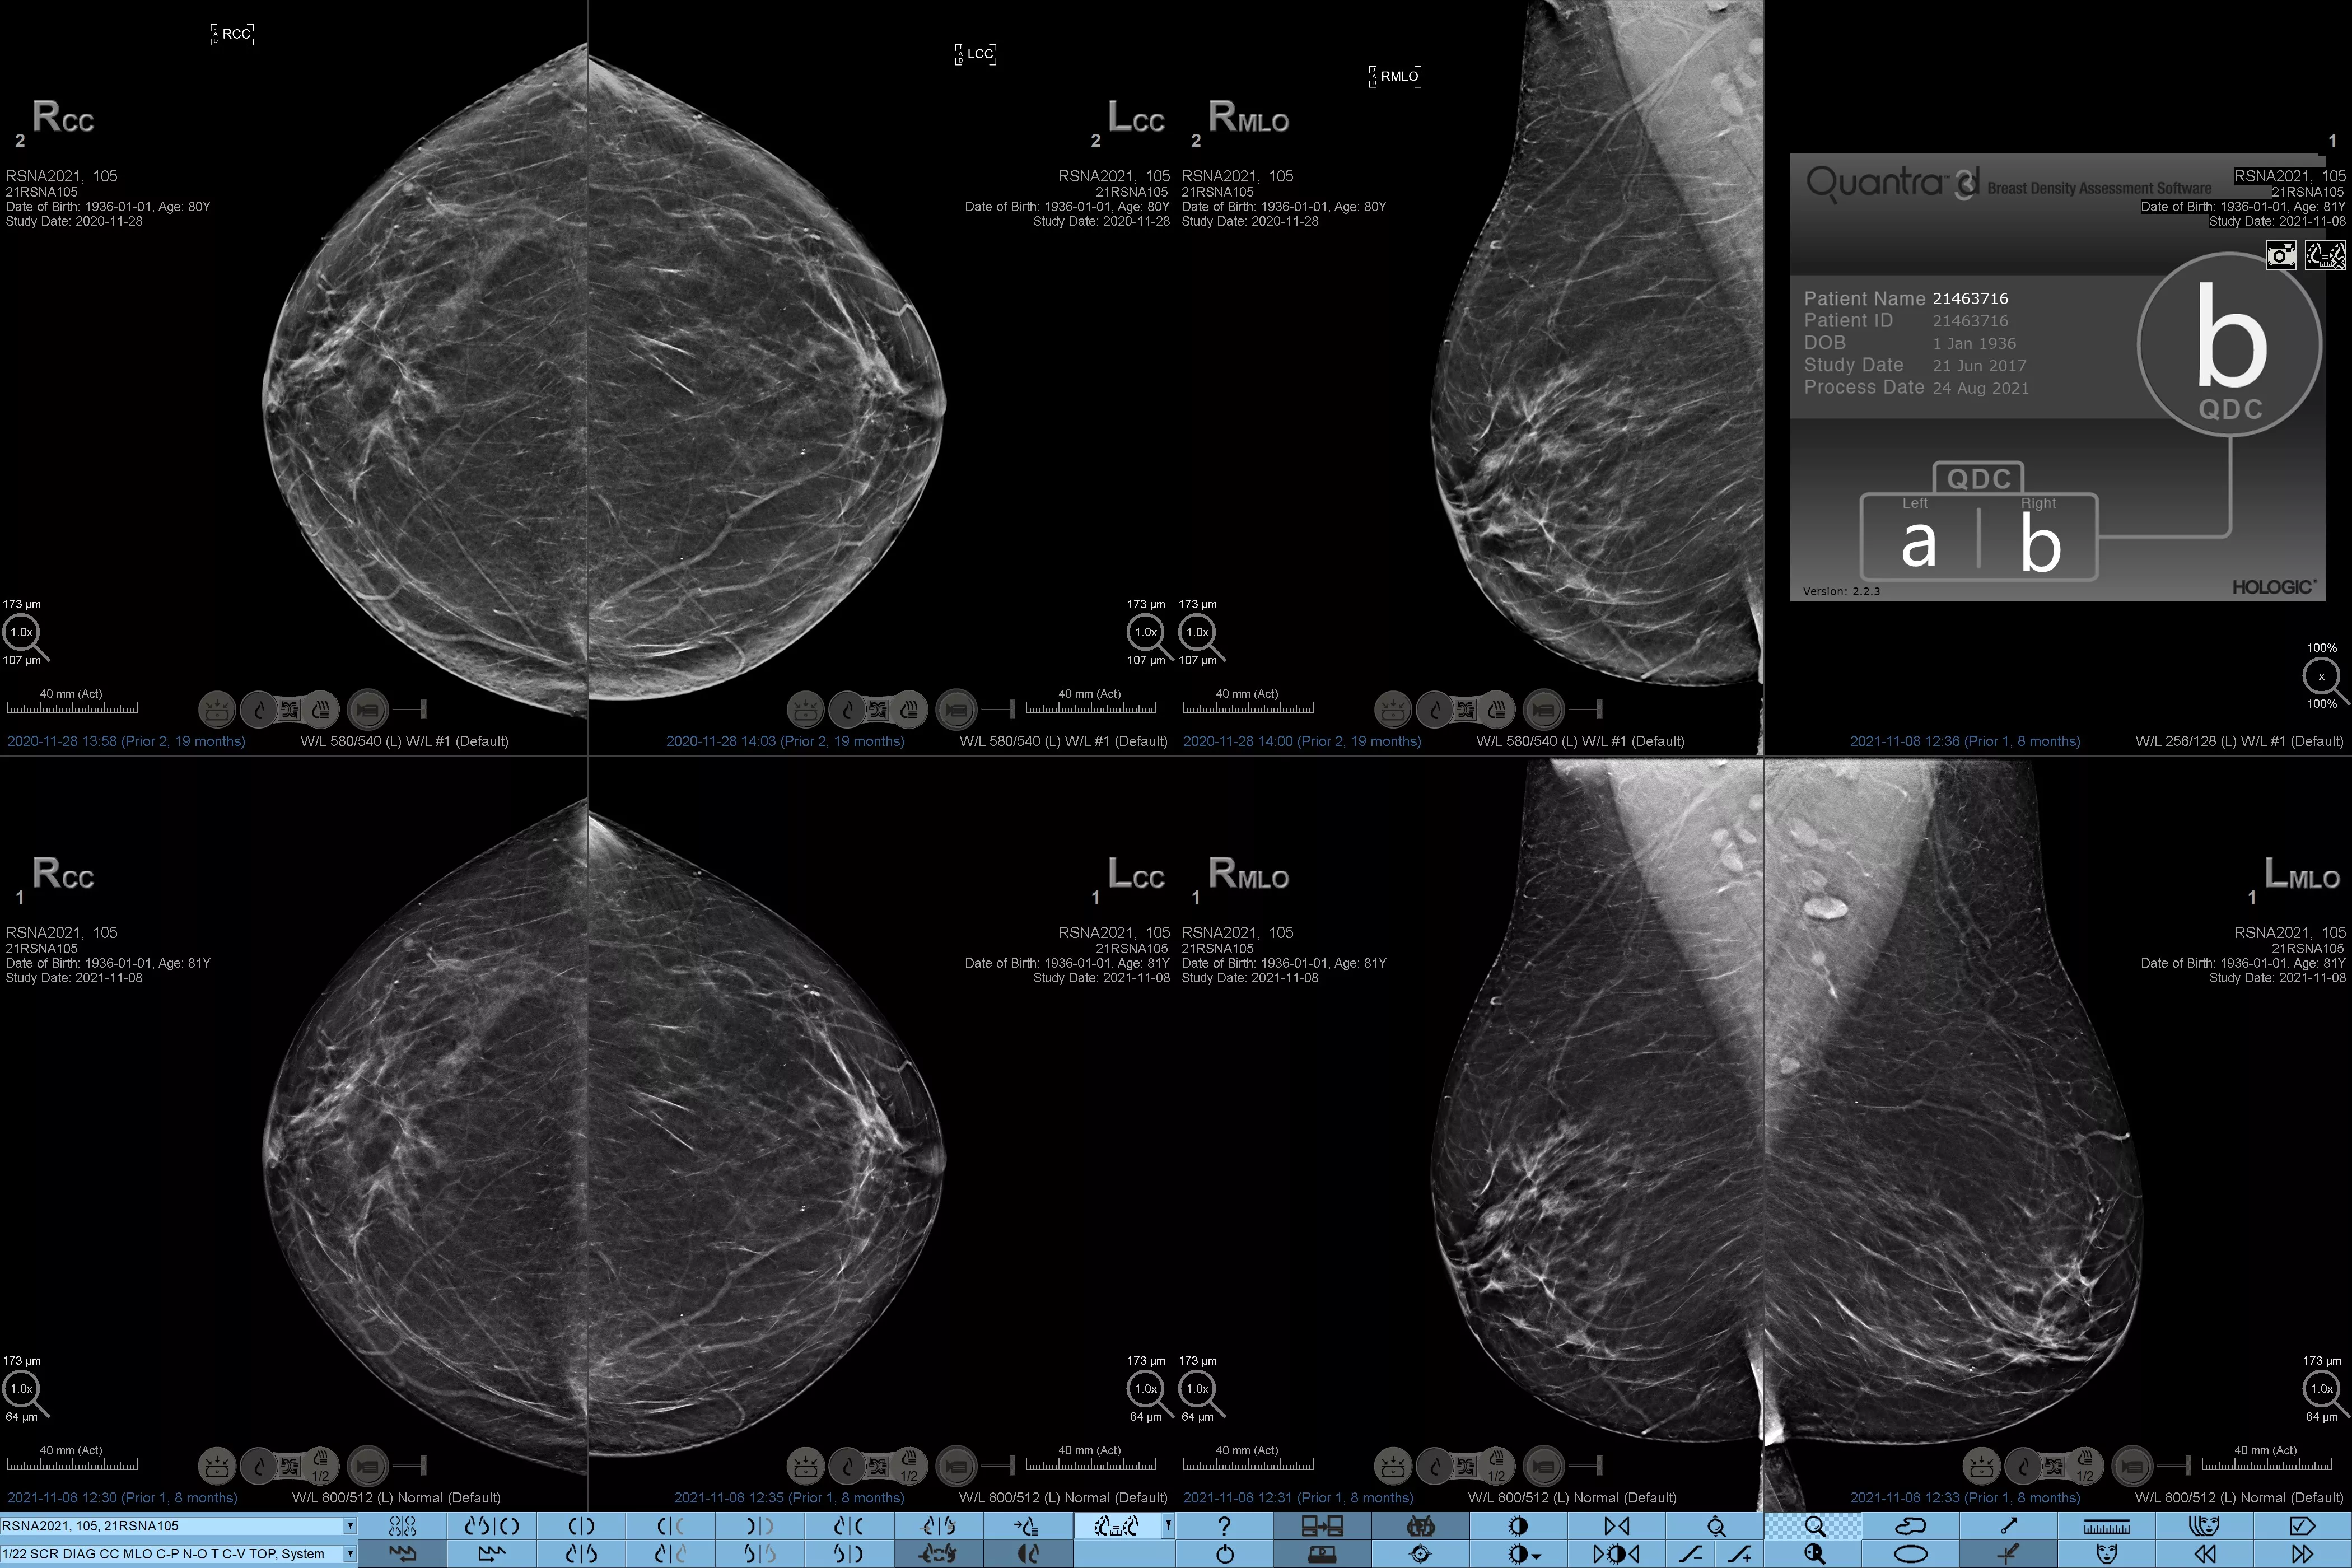

Higher breast density is known to increase a woman’s risk for breast cancer.1 The need for accurate, unbiased analysis is therefore critical. Powered by machine learning, Quantra technology software analyses both 2D™ and tomosynthesis images for distribution and texture of parenchymal tissue. It categorizes breasts in four breast composition categories consistent with guidance from the American College of Radiology (ACR) BI-RADS Atlas 5th Edition.2

Objective machine learning algorithm that assigns breast density category based on analysis of breast tissue texture and patterns.

*Scores are based on ACR BI-RADS categories, in line with the revised guidance by the American College of Radiation (ACR) BI-RADS Atlas 5th Edition. This accounts for pattern and texture, compared with volume, when determining density.

8. Breast composition categories as described in ACR BI-RADS Atlas.